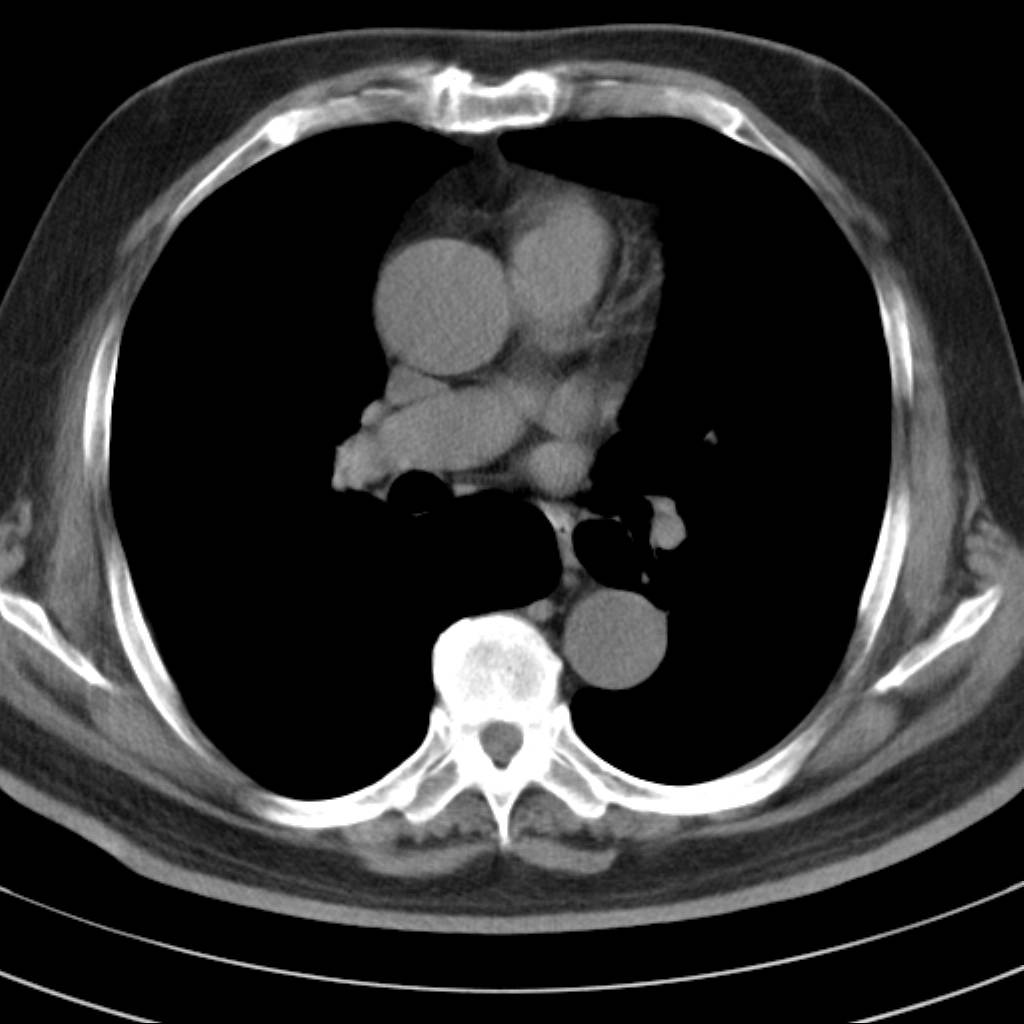

标题: CT18644:男,82岁,体检发现左肺阴影. [打印本页]

标题: CT18644:男,82岁,体检发现左肺阴影.

岁数太大,没有增强。麻烦见过的,给个诊断,顺便再说说病因

左侧中心型肺癌并粘液栓形成。很典型的。手套征。

支持 左肺上叶中央型肺癌并支气管内粘液栓形成。

支持考支气管扩张伴粘液栓,但导致粘粘液栓的病因有待进一步检查。支持左上叶支气管基部肿物,肺癌可能性大,但肿块似与肺动脉右支保持良好的伙伴关系,不除外为肺动脉扩张所致,建议增强。

左肺动静脉畸形,肺动静脉畸形(pavms)是肺血管发育异常,是肺动脉与肺静脉直接相通形成短路,通常包括一条供血动脉及一条或数条引流静脉,以及他们之间的异常血管团。约70%的患者伴发遗传性出血性毛细血管扩张症。 影像检查的目的在于确定病灶位置、大小、形态、数目。x线可表现为:1.结节型(直径小于3cm)2.团块型(直径大于3cm)3.弥漫型(肺内散在逗点状影),以团块状居多。 ct扫描可见单发或多发肺内结节,有的有蜿蜒迂曲的团块影,边缘光滑、锐利,增强ct扫描可见增粗、扭曲的血管影和/或类圆形的增粗的血管断面,甚至供血动脉及引流静脉。

考虑左肺上叶中央型肺癌并支气管内粘液栓形成。

支持 左肺上叶中央型肺癌并支气管内粘液栓形成,阻塞性肺炎

考虎左肺上叶中央型肺癌并支气管内黏液栓形成,不能增强是个遗憾,期待复查结果。

左肺上叶中央型肺癌